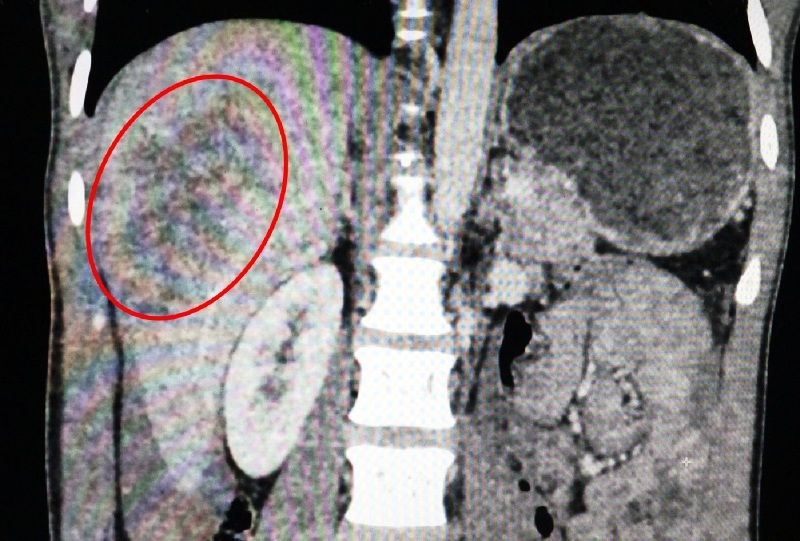

Ảnh chụp CT scanner vị trí gan của anh T. vỡ. |

Kết quả chụp CT scanner, bác sĩ nhận thấy gan của bệnh nhân bị vỡ nhiều đường phức tạp, chảy máu đầy trong ổ bụng.